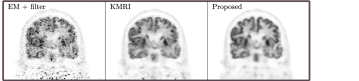

A 3D brain phantom from BrainWeb [31] was used in the simulation. Corresponding T1 weighted MR image was used as the prior image. The voxel size is 2×\times2×\times2 mm3superscriptmm3\mbox{mm}^{3} and the phantom image size is 128×\times128×\times105. To simulate mismatches between the MR and PET images, twelve hot spheres of diameter 16 mm were inserted into the PET image as tumor regions, which are not visible in the MR image. In this experiment, the last 5 min frame of a one-hour FDG scan was used as the ground-truth image. The computer simulation modeled the geometry of a Siemens mCT scanner. Noise-free sinogram data were generated by forward-projecting the ground-truth image using the system matrix and the attenuation map. Poisson noise was then introduced to the noise-free data by setting the total count level to be equivalent to last 5 min scan with 5 mCi injection. Gaussian post-filtering method (denoted as EM+filter) and the kernel method (denoted as KMRI) [12] were employed as comparison methods. Fig. 4 shows three orthogonal views of the reconstructed images using different methods. The kernel method and the proposed method both reveal more cortex structures compared to the EM-plus-filter method due to the boundary information provided by the MR priors. Compared to the kernel method, the proposed method can recover even more details of the cortices and the white matter regions are cleaner. Besides, the tumor uptake using the proposed method is higher and the tumor shape is closer to the ground truth. This means that even when there are mismatches between the PET and MR images, the proposed method can still recover the true PET intensities and shapes. Fig. 6(a,b) shows the contrast recovery coefficient(CRC). vs standard deviation (STD) curves for different methods. For both the gray matter region and the tumor region, the proposed method out-performs other methods.

Refer to caption

(a)

(b)

(c)

Figure 4: Three orthogonal slices of reconstructed images using different methods for the simulation brain dataset.